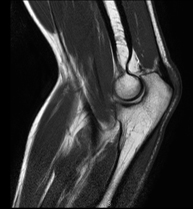

- RM Rodilla

Exploración para el estudio de lesiones en la articulación, como roturas meniscales y de ligamentos cruzados (unicamente detectables mediante esta prueba), condropatía o desgaste del cartílago y multitud de otras alteraciones derivadas de la actividad deportiva y los cambios degenerativos (osteoartrosis). Tiene una duración aproximada de 18 minutos. No emplea radiación ionizante.